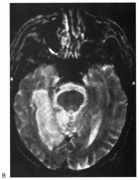

Fig. 5. Macula-splitting hemianopia. A 47-year-old man with AIDS and sudden onset of poor vision. A. Fields show complete left hemianopia. B. MRI shows lesion of right lateral occipital cortex, affecting distal optic radiations. Biopsy showed nonspecific encephalitis.

Fig. 6. Lesion of temporal optic radiation. Left superior quadrantanopia, respecting horizontal meridian (A), from infarct of right medial temporal lobe, in posterior cerebral artery territory (B). (From Rosen ES, Eustace P, Thompson HS, Cumming WJK [eds]: Neuro-Ophthalmology. London: Mosby, 1998.)